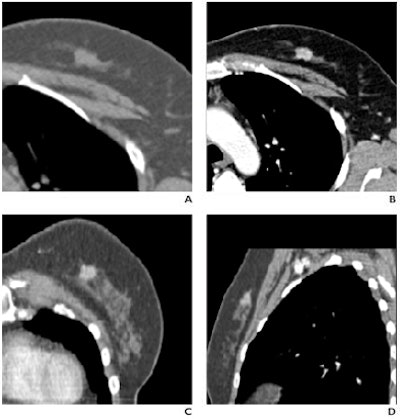

![]()  |

| Fifty-two-year-old woman with invasive ductal carcinoma in left breast. (A and B) Dynamic MDCT images at baseline (A) and one minute (B) after contrast administration depict an irregular lesion with homogeneous enhancement; evaluation of time-attenuation curve showed washout pattern. (C and D) Coronal and sagittal multiplanar reconstructions one minute after contrast administration show lesion in A and B located in upper left quadrant of breast, approximately 2 cm behind nipple. |